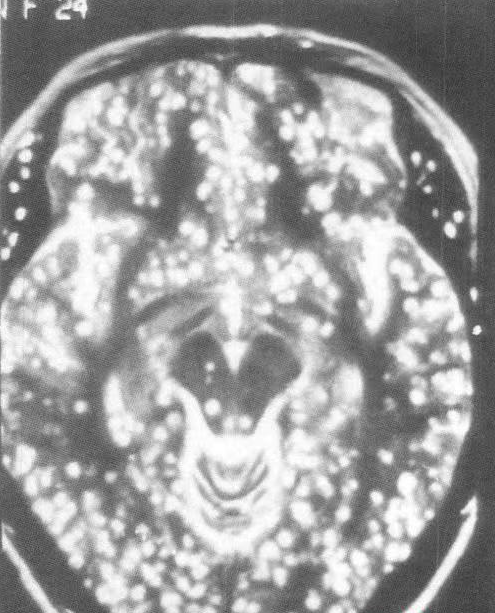

另位40多歲的張姓男子狀況更為嚴重,他因為頭部劇烈疼痛超過一個月而求診,起初只是靠服用止痛藥緩解,但後來發現即使加重劑量,藥效也愈來愈差。經過腦部掃描檢查後發現,他的腦中已經佈滿密密麻麻、難以計數的寄生蟲。醫療團隊追查病因後得知,張男長期食用僅經風乾處理、未經高溫烹煮的犛牛肉乾,導致蟲卵反覆進入體內,最終在腦部大量繁殖。